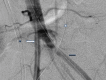

Arterioureteral fistula (AUF) is a direct communication between the ureter and an artery and is a rare cause of catastrophic, life-threatening haematuria. Fistulation may occur between the ureter and the abdominal aorta, common iliac, external and internal iliac, and inferior mesenteric arteries, and is typically observed in patients with a prior history of pelvic radiotherapy, oncological pelvic surgeries, aortoiliac vascular procedures, and pelvic exenteration. There is also an increased frequency of cases amongst patients who have undergone urological diversion surgeries and in those with chronic indwelling ureteric stents requiring repeated exchange. As AUF is so rarely encountered in clinical practice, the urologist may fail to appreciate its presence until late in the patient's presentation; such diagnostic delay is associated with high mortality and thus rapid clinical suspicion and investigative action are necessary. There are sporadic cases of this rare entity mentioned in literature. In this report, we present two cases as well as a review of the literature. A 73-year-old female presented with repeated episodic haematuria for a week in whom the cause of symptoms remained persistently elusive despite repeated imaging and operative approaches. An eventual diagnosis of a secondary right internal iliac-ureteral fistula was ascertained on a subsequent digital subtraction angiography of the renal tract. The fistula was embolised using an endovascular approach. The patient remained stable post emobilisation and was successfully discharged shortly after the procedure. In the second case, a 51-year-old female, presented with hematuria from her ileal conduit for a few days. Initially, the cause of symptoms was thought to be due to ureteric stents. During a change in her stents, brisk bleeding led to further investigation including an iliac angiogram confirming bleeding from the left common iliac artery. She had a covered common iliac artery stent, which successfully controlled her bleeding This report emphasizes the diagnostic difficulty of AUF, outlines the management principles of this rare disease, and aims to increase awareness of this rare yet potentially lethal phenomenon among practitioners of urology and interventional radiology.